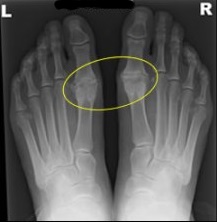

El hallux rigidus (HR) es una artropatía degenerativa de la articulación metatarsofalángica (MTF) del primer dedo del pie, caracterizada por la pérdida progresiva del movimiento articular, especialmente en dorsiflexión, acompañada de dolor y deformidad osteofítica. Es la segunda patología más frecuente que afecta al primer radio del pie, después del hallux valgus, con una prevalencia estimada del 2,5% en mayores de 50 años y una ligera predilección por el sexo femenino.

4. Clasificación Radiológica y Diagnóstico Diferencial

4.1. Clasificación de Regnauld (Grados I-III)

Grado | Hallazgos Clínicos | Hallazgos Radiológicos |

---|---|---|

I (Leve) | Dolor ocasional, movilidad > 50% | Osteofitos mínimos, espacio articular conservado |

II (Moderado) | Dolor frecuente, rigidez marcada | Osteofitos dorsales, esclerosis subcondral, pinzamiento articular |

III (Severo) | Dolor en reposo, anquilosis funcional | Pérdida completa del espacio articular, geodas, deformidad articular |